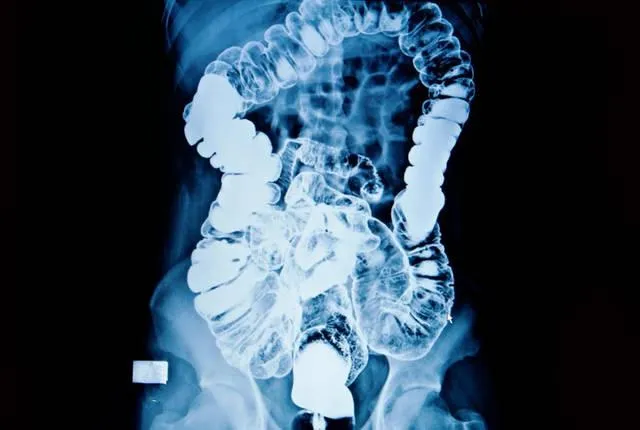

胃病诊断:钡餐检查里的 "钡" 家学问

你有没有陪家里长辈做过消化道检查?医生常会让你喝一种白白的 "造影剂",这就是我们常说的钡餐。

很多同学好奇,钡是重金属啊,喝下去不会中毒吗?这就要从钡餐的成分说起了:我们用的钡餐,是硫酸钡(BaSO₄)。

1. 不溶于水,也不溶于酸 —— 胃酸再多也奈何不了它

2. 无毒,不会被人体吸收

3. X 射线穿不透,能在片子上清晰显示出消化道的轮廓